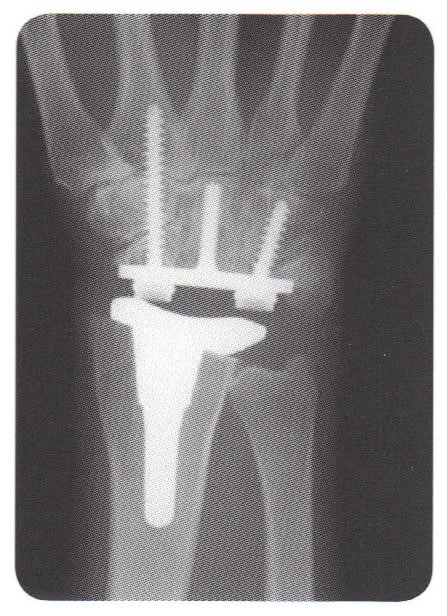

Om operationen